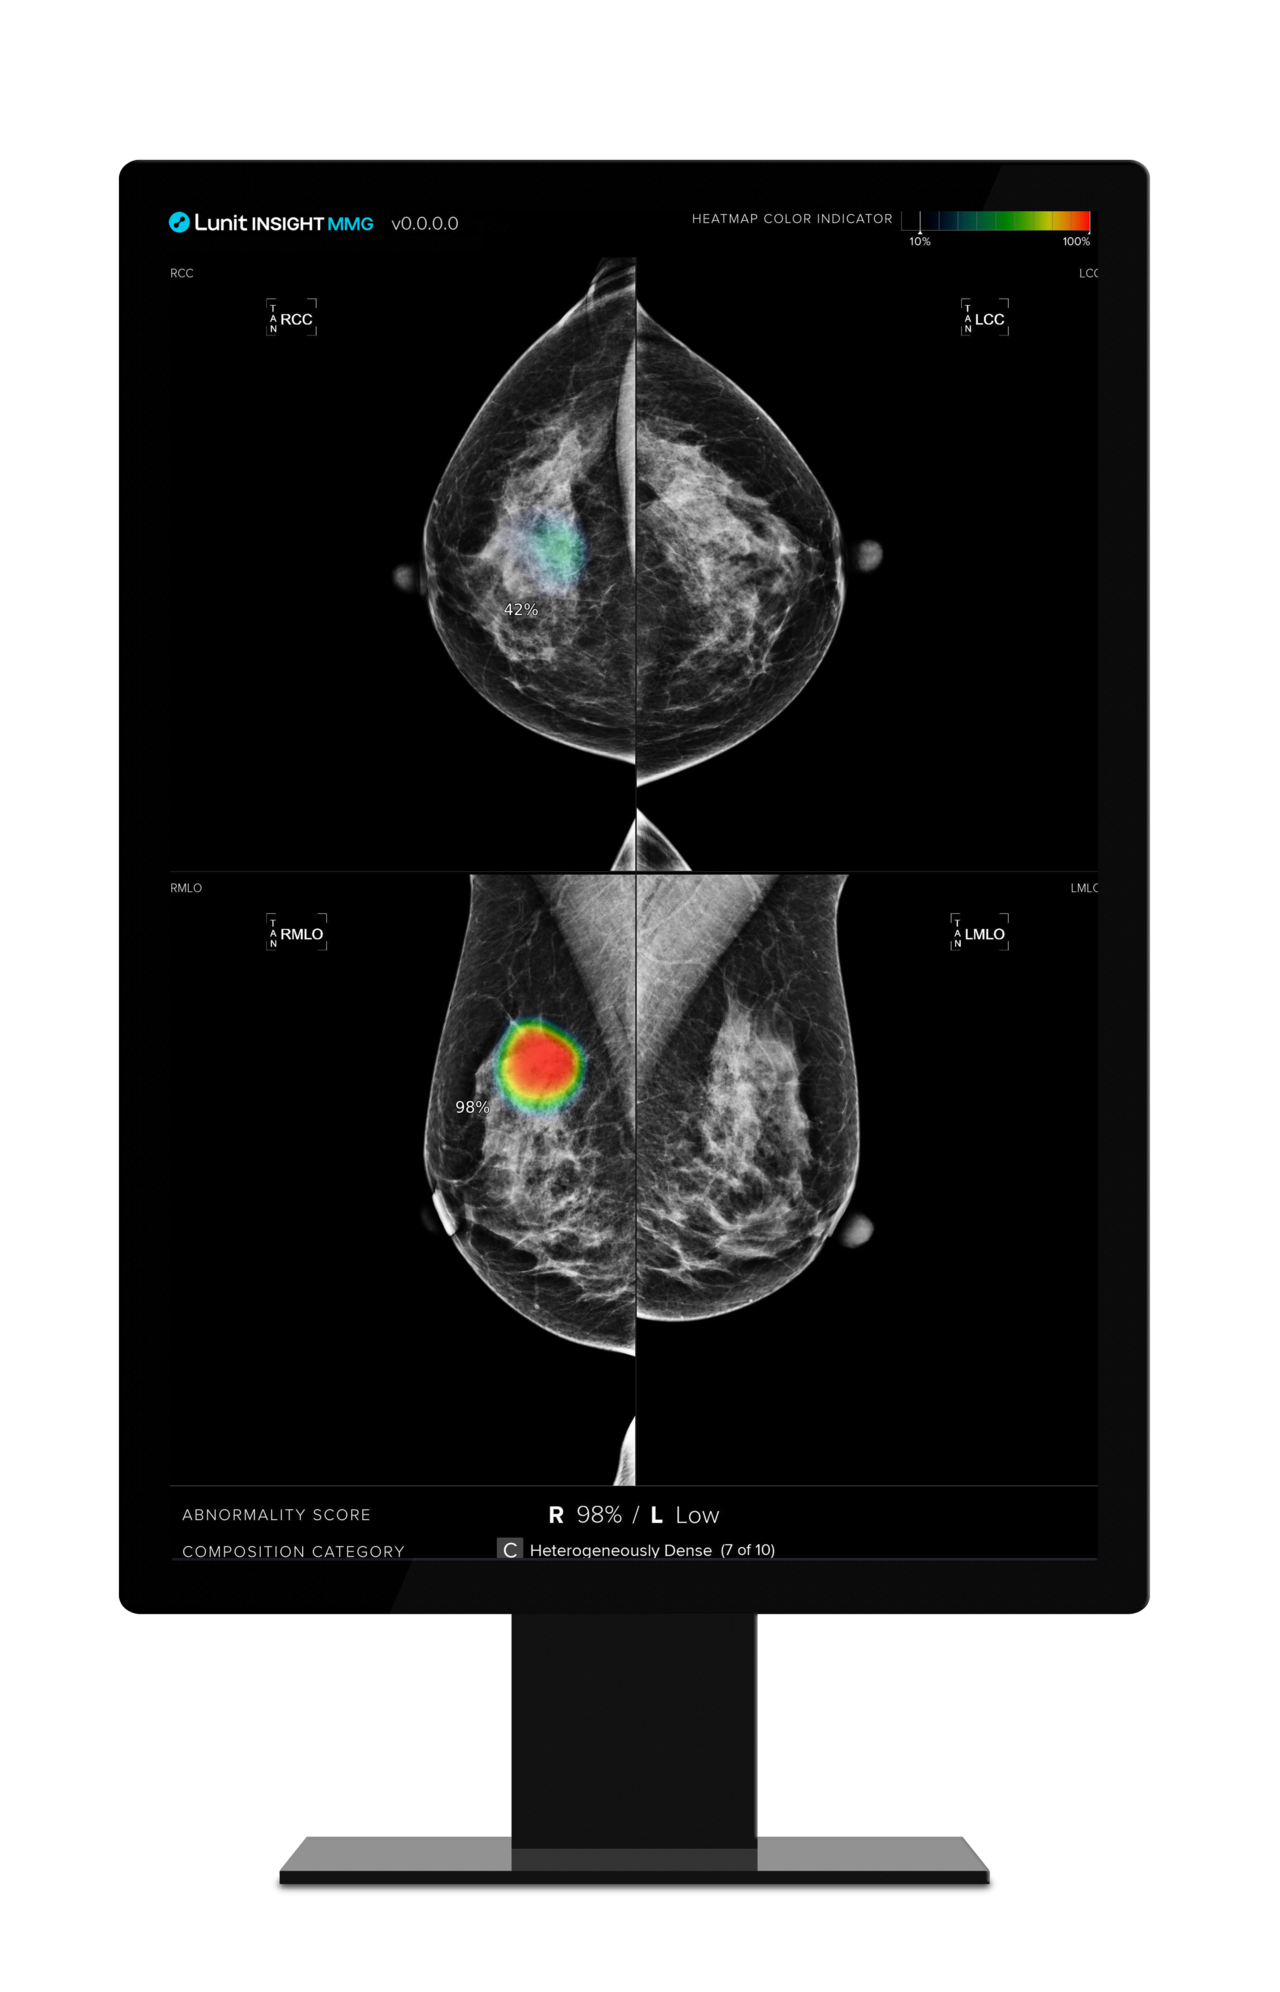

루닛은 지난 2021년 아그파 헬스케어와 MOU를 체결, 아그파 헬스케어 제품에 탑재할 AI 영상분석 패키지 솔루션을 개발했다. 두바이 공공의료원(DAHC)과 3년간 검토 및 평가 작업을 진행한 결과 유방촬영술 AI 영상분석 솔루션 '루닛 인사이트 MMG'를 기반으로 하는 통합 이미징 플랫폼 '아그파 헬스케어 엔터프라이즈 이미징'을 처음으로 공급하게 됐다고 설명했다.